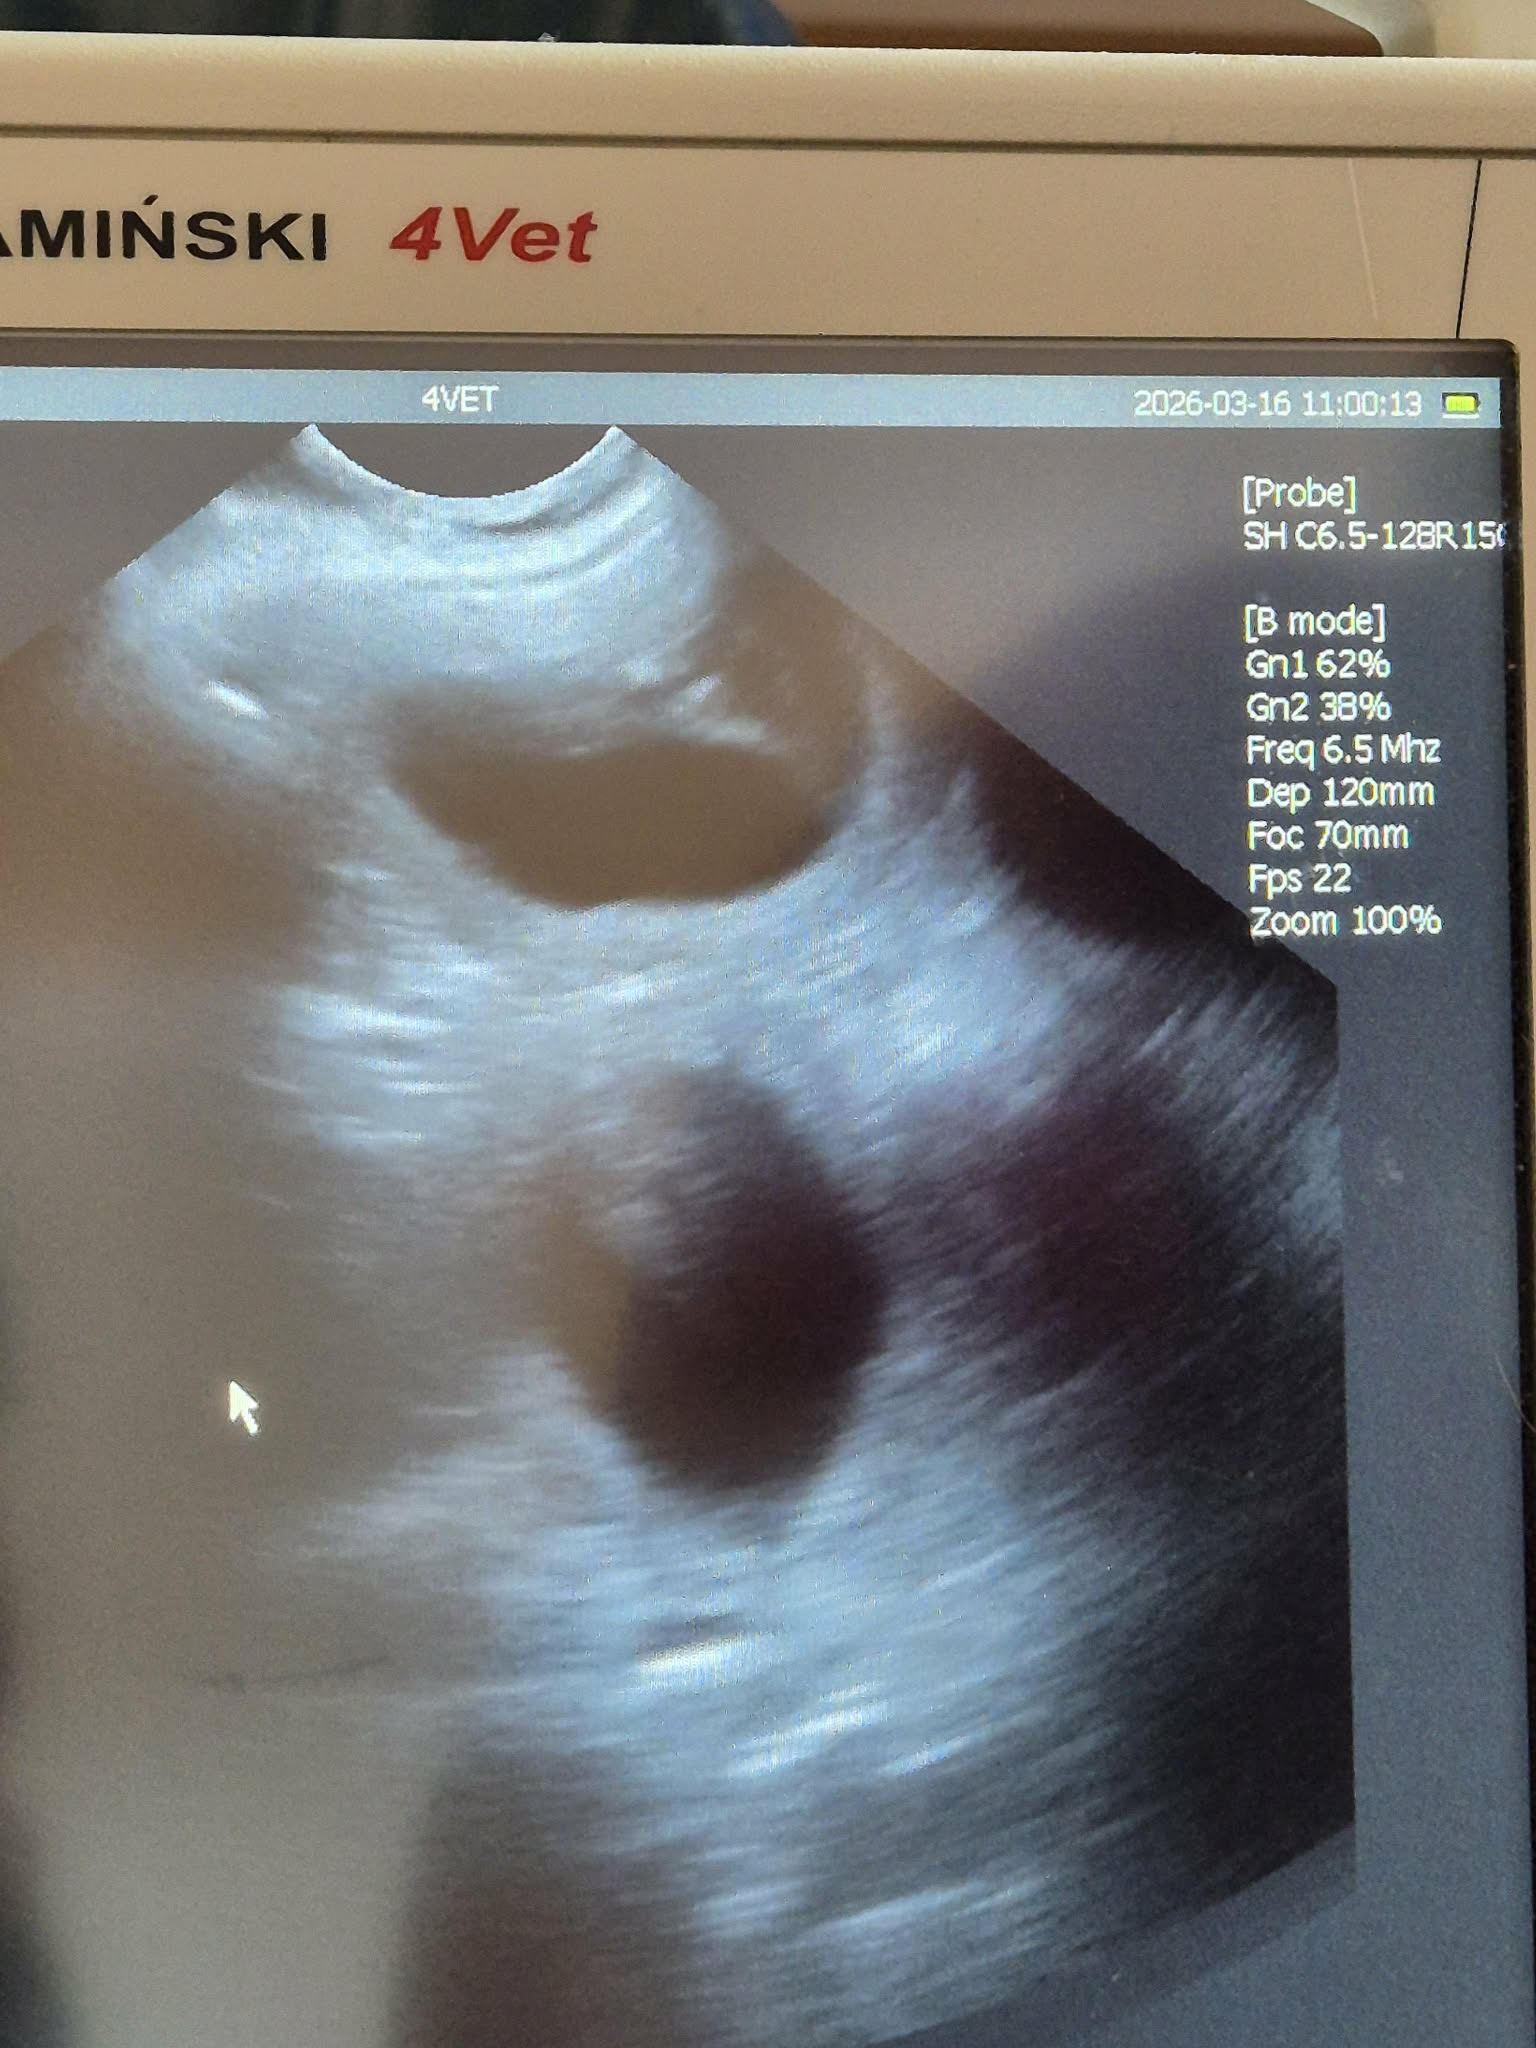

2026-03-16 I dag var det dags för ultraljud på Socker, och visst fanns det en hel hög med valpar i magen på henne!